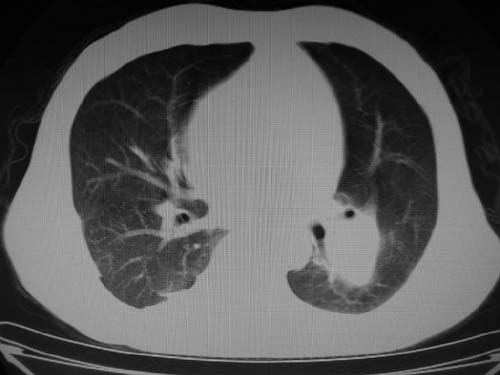

标题: CT17069:M80Y,请战友们看看像啥 [打印本页]

标题: CT17069:M80Y,请战友们看看像啥

男,80岁

肺a高压征[左肺a狭窄?];肺,胸膜tb

右肺上叶结核;左肺门占位?建议增强扫描.

左下肺静脉扩张,原因?建议cta

左肺动脉异常增粗,建议增强。

1)考虑肺动脉狭窄。2)右肺上叶继发性肺结核。3)右侧胸膜增厚、钙化,左侧胸膜反应。

肺动脉瘤。建议先行ct增强扫描

左肺动脉异常增粗,考虑肺动脉狭窄可能。

右肺上叶继发性肺结核。

右侧胸膜增厚、钙化,左侧胸膜反应。

左肺动脉异常增粗,建议ct增强,排除肺门肿瘤

右侧胸膜增厚、钙化,左侧胸膜反应

双肺陈旧性病变,左肺动脉高压.

1)考虑左肺动脉瘤可能性大,建议增强。2)右肺上叶继发性肺结核。3)右侧胸膜增厚、钙化,左侧胸膜反应。

肺动脉段突出,左右肺门不等大,左肺门明显增大,肺动脉干及左肺动脉明显增宽,考虑先天性肺动脉狭窄瓣膜狭窄型。

)考虑肺动脉扩张,右心室增大,主动脉弓段正常位弓后段明显变小(不会是动脉导客未闭吧,不知患者有何症状病史)0。2)右肺上叶继发性肺结核。3)右侧胸膜增厚、钙化,左侧胸膜反应。

右肺上叶尖段结核;左肺下叶占位?建议增强扫描。右侧胸膜增厚;右肺局限性肺气肿。

结合患者年龄,不除外左下肺扩张性动脉瘤,建议胸透是否有扩张性博动,以便确诊。

肺动脉高压,左肺动脉瘤样扩张。

肺a高压